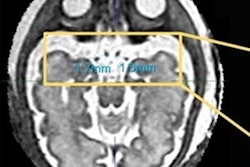

- Very low-dose imaging exams such as mammography and radiography, excluding imaging of the abdomen and pelvis, do not require pregnancy verification. The same goes for CT imaging outside the abdomen and the pelvic/hip area.

- Pregnancy status should be verified prior to imaging that includes the abdomen and pelvis in the field of view, such as fluoroscopy, CT, and radiography.

- Once a pregnancy is established, a radiologist should consider whether the exam is needed or can be delayed until after delivery, if there are alternative exams available (ultrasound or MRI), and if changes can be made to protocols to decrease radiation dose.